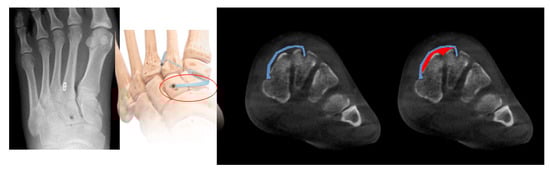

Comparison Between Standard Screw and Internal Brace in Treatment of Subtle Lisfranc Injury

by Dong-Il Chun, Sanghoon Lee, Jaeho Cho, Sung Hyun Lee, Jeoung Wook Lee and Young Yi

J. Clin. Med. 2026, 15(3), 1018; https://doi.org/10.3390/jcm15031018 - 27 Jan 2026

Background: Subtle Lisfranc injuries are low-energy, purely ligamentous lesions increasingly recognized in active patients; although screw fixation is common, Internal Brace (IB) flexible fixation is an alternative. Methods: In this multicenter retrospective study (2014–2021), 65 patients with subtle ligamentous Lisfranc injury (C1–M2 diastasis [...] Read more.

Background: Subtle Lisfranc injuries are low-energy, purely ligamentous lesions increasingly recognized in active patients; although screw fixation is common, Internal Brace (IB) flexible fixation is an alternative. Methods: In this multicenter retrospective study (2014–2021), 65 patients with subtle ligamentous Lisfranc injury (C1–M2 diastasis < 5 mm) underwent standard screw (SS, n = 35) or IB fixation (n = 30). Outcomes included AOFAS and VAS, standing radiographs and weight-bearing CT (WBCT) diastasis, pedobarography (4–6 months), and complications. Results: Demographics and injury mechanisms were similar. Both groups improved from preoperative status to final follow-up (p < 0.05). At 6 months, IB had higher AOFAS and lower VAS than SS (p < 0.05). Final stability was comparable: standing C1–M2 diastasis 2.54 mm (IB) vs. 2.55 mm (SS); WBCT dorsal 1.26 vs. 1.21 mm and plantar 3.58 vs. 3.42 mm (all NS). Pedobarography showed no significant side-to-side differences in either group. Complications favored IB: SS had screw breakage 11.4% (4/35), recurrent diastasis 2.9% (1/35), and early arthritis 5.7% (2/35); IB had no implant breakage, no severe recurrent diastasis, and no early arthritis. Conclusions: In this Level III study, IB fixation was associated with better 6-month clinical outcomes with similar final radiographic stability and fewer hardware-related complications versus SS. Full article

(This article belongs to the Section Orthopedics)

Show Figures

Figure 1